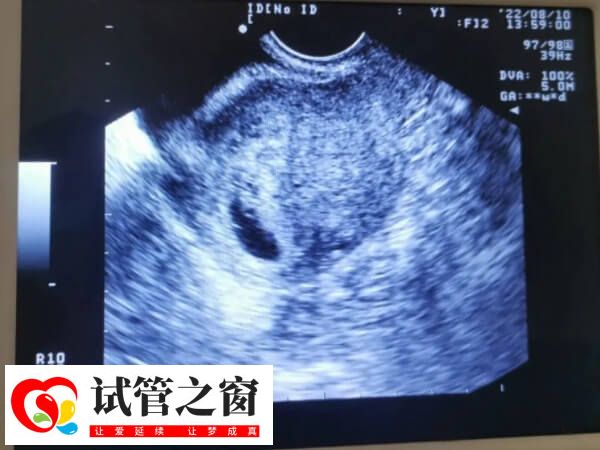

试管婴儿二超检查胎芽长度

胎芽是妊娠早期形成的组织,是早孕时胚胎发育时期的一个必经的阶段,通常情况下,试管二超的时候胎芽在1.3-1.7厘米才是比较合适的,此情况下说明胚胎发育是非常良好的,而不足1.3cm的胎芽就偏小了,但是此情况下,若是女性hcg激素翻倍情况正常,而且B超检查的孕囊大小等数值与陪她是符合的,那么试管二超胎芽不足1.3厘米就是正常的。